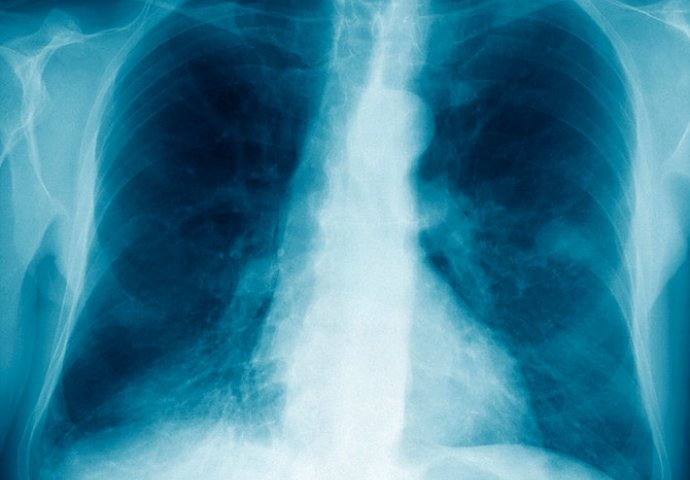

GODINAMA JE IMAO PROBLEMA SA PLUĆIMA, ali nije ni slutio da je dvije decenije nosio nešto JEZIVO u svom tijelu!

Naime, jedan muškarac je prije 20 godina progutao zatvarač hemijske olovke, a tek nedavno je nakon odlaska ljekaru shvatio šta je godinama nosio u svom tijelu.

Svih ovih godina imao je probleme sa disanjem, mučio ga je hronični kašalj, ali su smetnje bile prolazne.

Situacija se ove godine naglo pogoršala. Muškarac čije je prezime Vang počleo da je da iskašljava krv.

"Uvijek sam kašljao i imao plućne infekcije, ali sada sam morao prvi put da reagujem zbog iskašljavanja krvi", ispričao je za kineske medije, a prenosi "Miror".

To ga je natjeralo da ode lekaru. Ljekarski tim, predvođen doktorom Zuom Kangrenom,ultzrazvučnim pregledom je pronašao strano tijelo u plućima ovog muškarca.

Hitnom intervencijom je čep uklonjen.